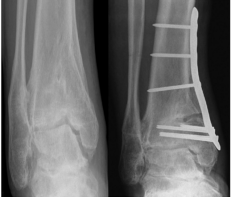

对于保守治疗无效且病情严重的患者,可能需要考虑手术治疗。手术方法包括关节镜手术清理关节腔、踝关节融合、踝关节置换等。